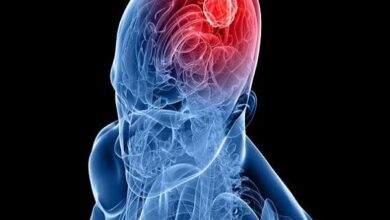

آلودگی هوا با تومورهای مشترک مغز همراه است – آژانس خبری مهر | اخبار ایرانی و جهانی

محققان گزارش دادند كه به نظر می رسد چندین نوع مختلف آلاینده هوا ، از جمله آلودگی ذرات و دی…